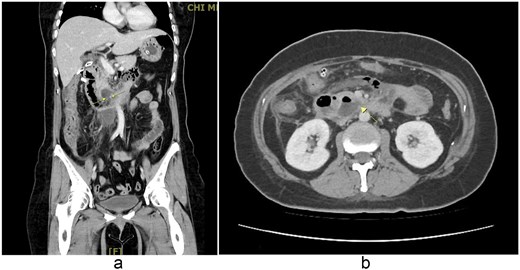

A 48-year-old woman with adenomyosis and prior gynecologic surgeries was diagnosed with influenza A at a local hospital on 21 August 2025. On 26 August, she presented with 4 days of diffuse abdominal pain, fever, chills, and nausea. Computed tomography (CT) revealed intra-abdominal free air, suggesting hollow organ perforation (Fig. 1). Retrospective review of the initial CT demonstrated subtle indirect findings, including retroperitoneal fat stranding and mild wall thickening of the third portion of the duodenum, without definite localization of the perforation. She received intravenous piperacillin–tazobactam and underwent emergency surgery.

(a, b) Contrast-enhanced abdominal CT scan (26 August 2025). Imaging demonstrates retroperitoneal free air with suspicion of perforation in the retroperitoneal region.